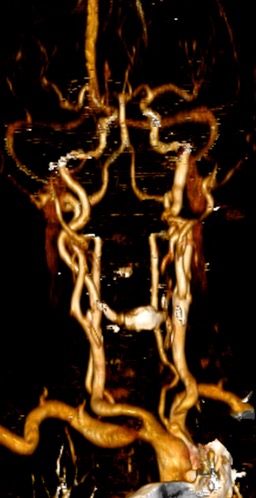

- analiza vasculaturii capului și a gâtului, incluzând arcul aortic și emergențele arterelor cervicale;

- evidențiază și evaluează stenozele vasculare;

- poate face diferențierea între un tromb ocluziv total, subocluziv sau stenoză aterosclerotică – patologie trombo-stenotică.

Evidențierea imagistică completă a arborelui arterial de la arcul aortic până la vertex în evaluarea atât a ocluziilor acute, cât si a stenozelor cronice poate fi realizată în timpul încărcării maxime cu contrast (peak).

Angiografia CT în afecțiunile arteriale extracraniene:

Angiografia CT și RM sunt minim invazive (se evită complicațiile inerente cateterizării invazive), sunt mai rapide și mai ieftine decât angiografia RX tradițională.